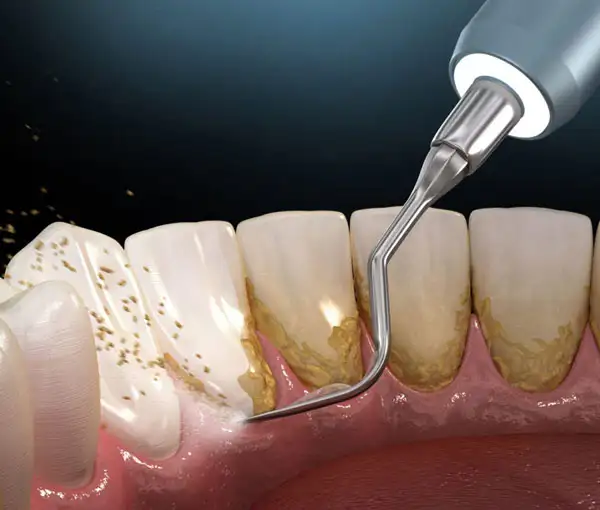

Professional removal of plaque, tartar, and stains to prevent gum disease, bleeding gums, bad breath, and tooth decay. Polishing smoothens the teeth, making it harder for bacteria to stick. Regular cleaning keeps your smile bright and your gums healthy. Recommended once every 6 months for optimal oral hygiene.